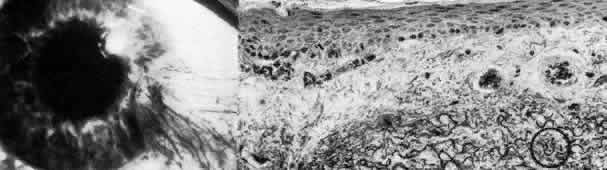

Sclerocornea

In sclerocornea (Fig. 4), the limbus is ill-defined since opaque scleral tissue with fine vascular conjunctival arcades extends into the peripheral cornea. A broad range of corneal involvement is possible, with the most extreme being complete sclerification of the cornea. Ninety percent of cases are bilateral, although generally asymmetric. Most cases are sporadic; there is no known heredity. Sclerocornea is nonprogressive and must be differentiated from interstitial inflammatory conditions and arcus juvenilis (congenital peripheral lipid deposition, also known as anterior embryotoxon). Sclerocornea is associated with cornea plana in approximately 80% of cases.44 Other associated ocular abnormalities include microphthalmos, iridocorneal synechiae, persistent pupillary membrane, dysgenesis of angle and iris, congenital glaucoma, colobomas, and posterior embryotoxon of the fellow eye.45 Somatic abnormalities sometimes occur along with associated chromosomal abnormalities; they include mental retardation, deafness, and craniofacial, digital and skin abnormalities.44

Fig. 4. Sclerocornea. Schematic drawing of ocular features Top left. In a minimally affected patient with additional findings of ptosis, strabismus, and hearing loss, only the peripheral cornea is opacified. Top center. In this advanced case with chromosomal translocation and multiple congenital abnormalities, the entire cornea is sclerified and the fine vascular arcades extend centrally from the conjunctiva and sclera. Top right. Light micrograph of anterior cornea shows edematous disorganization of epithelium, fragmentation of Bowman's membrane (B), and interstitial vascularization (V) (hematoxylin-eosin, × 200). Middle left. Transmission electron micrograph of normal human corneal stroma is shown for comparative purposes. Note uniform 240- to 260-nm collagen fibril diameter (× 50,000). Middle right. Transmission electron micrograph of sclerocornea at same magnification shows disorganized array of collagen fibrils that measure as much as three times normal diameter (× 50,000). Bottom. Transmission electron micrograph of posterior cornea shows abnormal Descemet's membrane of less than 1μm thickness (DM, bracketed) and attenuated endothelial cells (× 10,500). (Schematic. Grayson M: Diseases of the Cornea, p 32. St. Louis, CV Mosby, 1979; Top center and right. Rodrigues MM, Calhoun J, Weinreb S: Sclerocornea with an unbalanced translocation [17p, 10q]. Am J Ophthalmol 78:49, 1974)

Ultrastructural studies22,46,47 have shown the involved stroma to assume the morphologic features of scleral tissue, with irregularly arranged collagen fibrils of variable and immensely enlarged diameter for corneal tissue (up to 150 nm, comparable to normal scleral collagen). The precise lamellar organization of normal corneal stroma is not present; thus optical clarity is not achieved. Various abnormalities of endothelium and Descemet's membrane exist, from attenuation to focal absence. Descemet's membrane is generally thin, with multilaminar deposition of basement membrane-like collagen.

Pathophysiologically, sclerocornea may result from developmental arrest of limbal differentiation during neural crest migration, as occurs with the other mesenchymal dysgeneses.22